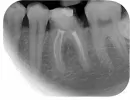

Мне 31 год. Никаких болевых симптомов в 36-ом зубе. Этот зуб лечил 3-4 года назад. Зуб беспокоил, пришлось лечить, и удалить нерв. Сейчас откололась стенка этого зуба, и режет щеку.

Посетил стоматологию, VIP уровня, сделал прицельный снимок 36-го зуба. Мне сказали, что нужно всё переделывать, удалять оставшуюся часть зуба, распломбировать каналы, извлечь инструмент, перелечивать. Сказали, возможно, воспаление. Сказали, нужно установить штифт, коронку. И внезапно предъявили круглую сумму.

Затем я обратился в другую клинику, средне статистическую. Сказали, нет смысла в переделке пока что, каналы пролечены, склерозированный, воспаления нет, пломба стоит вполне хорошая, и будет достаточно реставрации со штифтом в широкий канал и нарастить недостающую часть зуба. Избежать лишнего вмешательства, времени на посещения и расход.

Нужно ли повторное эндолечение, или подойдёт реставрация?

Так как разрушена большая часть коронковой части зуба, то необходимо зуб покрыть коронкой. Для этого необходимо укрепить его культевой вкладкой или штифтом. Так как каналы пролечены не идеально, не до верхушек корней, то вмешательство может привести к развитию воспалительного процесса.

В идеале необходимо почистить каналы и вновь запломбировать. Но вы должны понимать, что 100% гарантии на перелечивание такого зуба врач дать не может, но удалять зуб, не попытавшись его сохранить тоже неправильно.